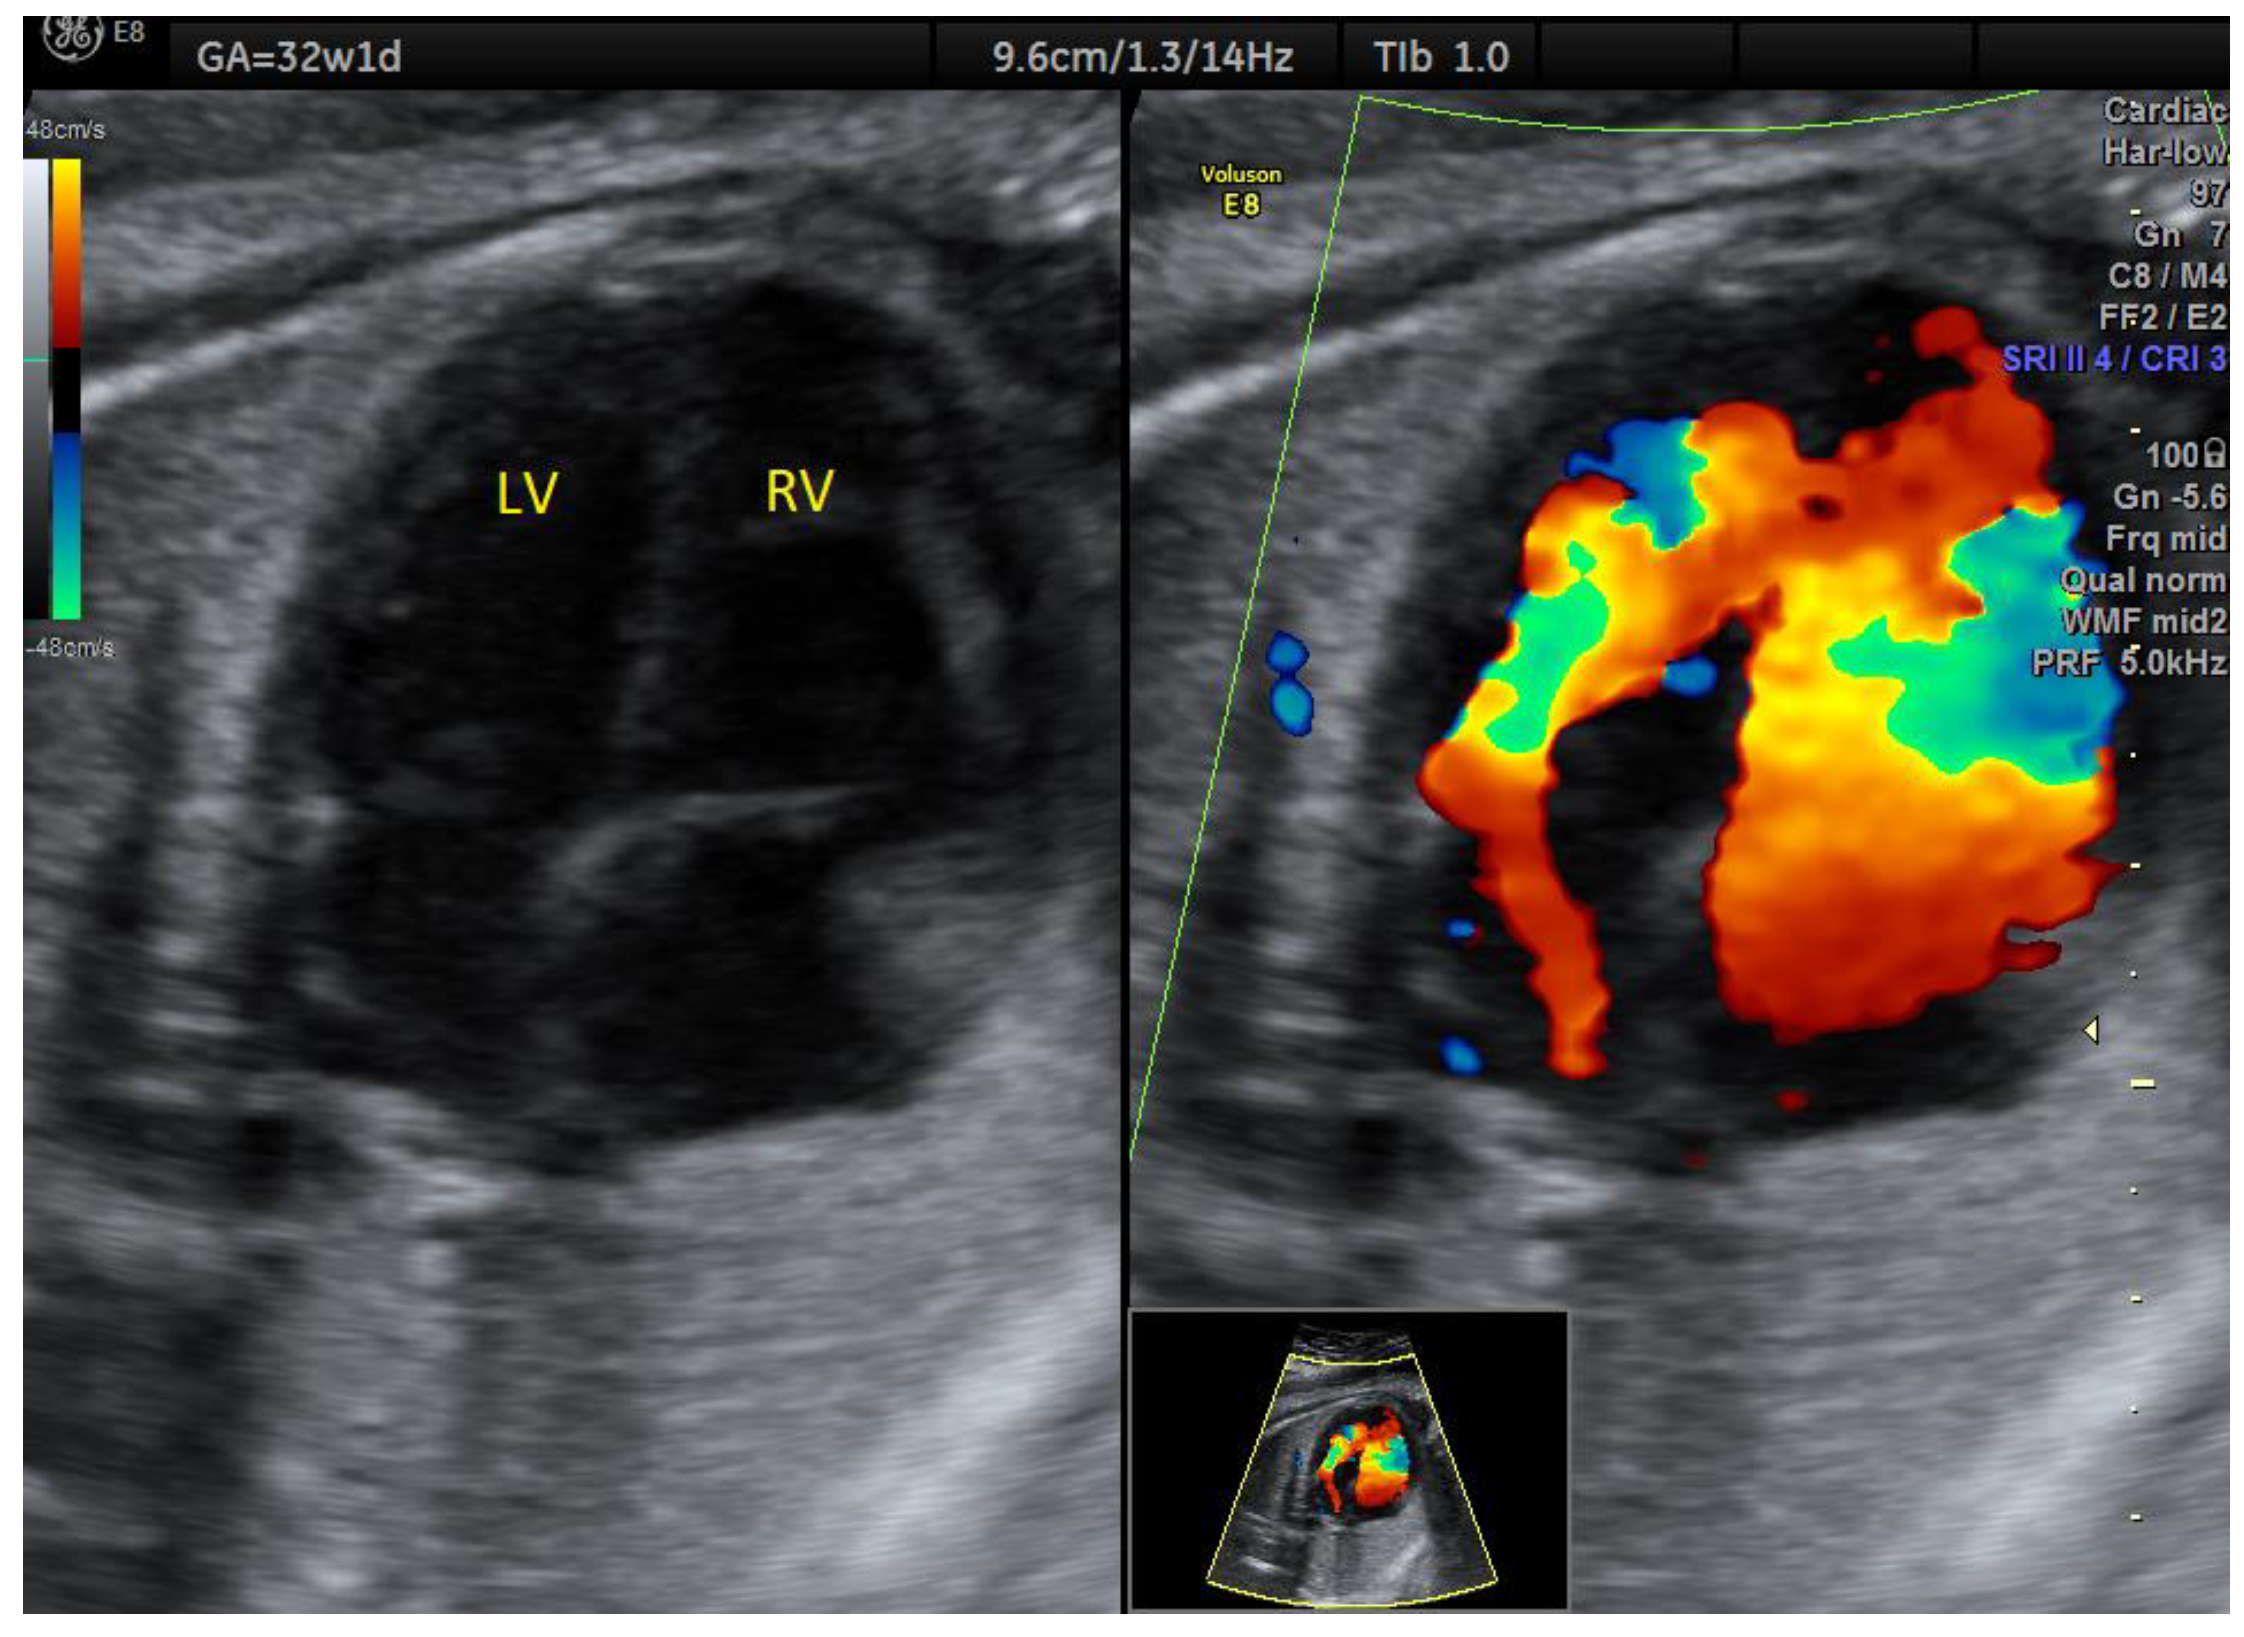

| HLHS | 1 | mitral atresia + aortic atresia | - | 4C | + | 0 | 1 | 0 | 1/1 |

| PA/IVS | 1 | - | - | 4C | + | 0 | 0 | 1 | 1/1 |

| Grayscale 4C only | 47.8% (22/46) | 57.1% (8/14) |

| Grayscale 3VT only | 36.9% (17/46) | 21.4% (3/14) |

| Color 3VT only | 58.6% (27/46) | 14.2% (2/14) |

| Grayscale 4C + 3VT | 71.7% (33/46) | 0% (0/14) |